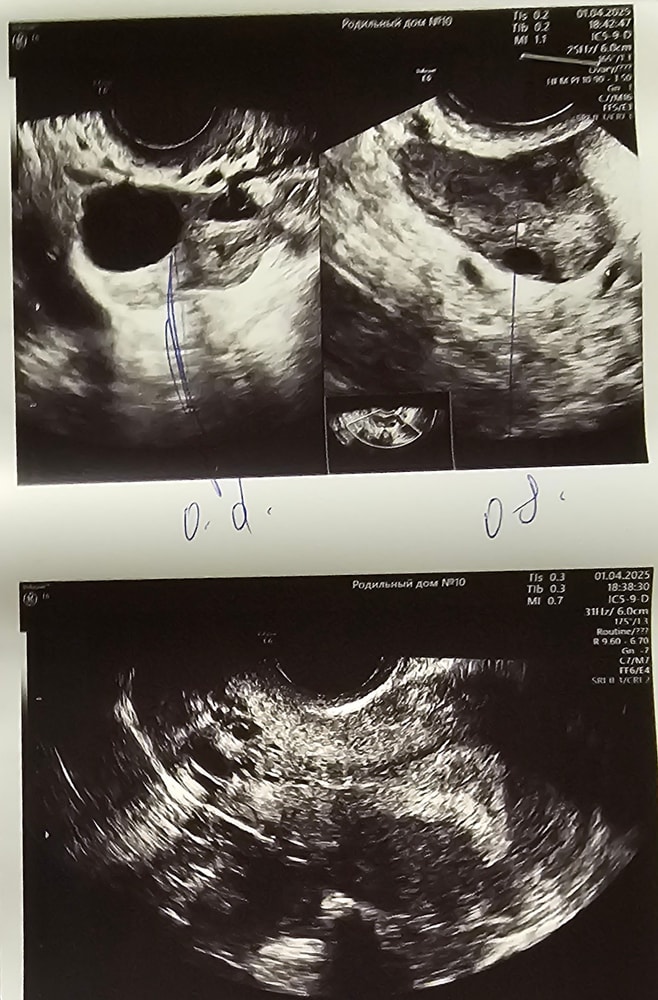

Конечно ХГЧ. Если па был до овуляции. То через 10 дпо ХГЧ сдать. Второй фолликул может не лопнуть а перерасти в кисту так как прогестерон уже есть. А может и лопнуть тут не угадать по разному ситуации развиваются. Смотря какой у вас сейчас прогестерон и на какой размер фолликула он начал вырабатываться. Но то что фолликул 23 и нет признаков овуляции возможно он перерастет в кисту. Жт от первого разрыва фолликула не очень большого размера. Либо только расцветает, либо недостаточно прогестерона. Я бы сдала кровь посмотрела его уровень. Какой сейчас дпо??

Хомячиха, я так понимаю один фолликул не лопнул? С другой стороны там жёлтое тело 15мм. Остаётся только ждать 😪

Гала, да не лопнул и он уже 23 есть вероятность, что перерастет в кисту.

Хомячиха, а второй я так понимаю лопнул, но маленькое жёлтое тело. Теперь понятно. Спасибо!

Гала, да один лопнул и маленькое жт, один не факт ,что лопнет от многих факторов зависит.

Когда ждать овуляции?все ли в норме для 8дня цикла?3бхб,ставили гипоплазию эндометрия,второй цикл го УЗИ